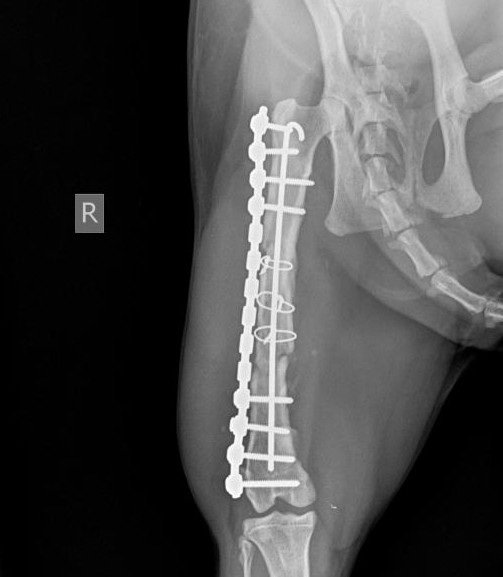

Knochen- und Gelenkchirurgie

Zum Gebiet der Knochen- u. Gelenkchirurgie zählen beispielsweise die Versorgung von Frakturen, Gelenkstraumen oder die Versorgung von Bänderrissen, wie z. Bsp. Kreuzbandrisse. Hierbei kommen modernste Techniken und Materialien (z. B. Implantate) zum Einsatz.